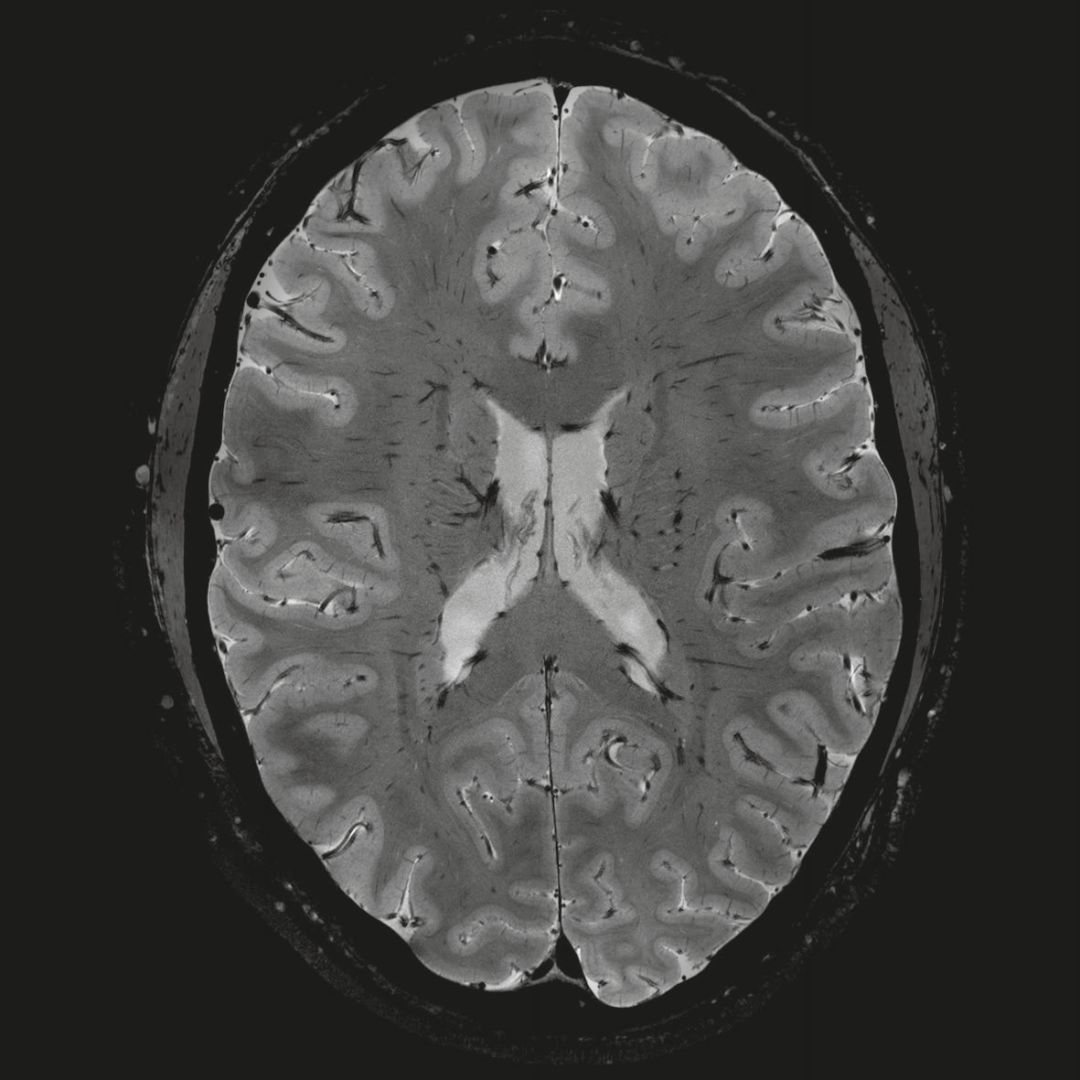

0.8毫米的各向同性分辨率:精確劃分灰質(zhì)和白質(zhì)

超精細(xì)的解剖細(xì)節(jié):T2對比

0.17 x 0.17 x 0.8毫米分辨率超高。